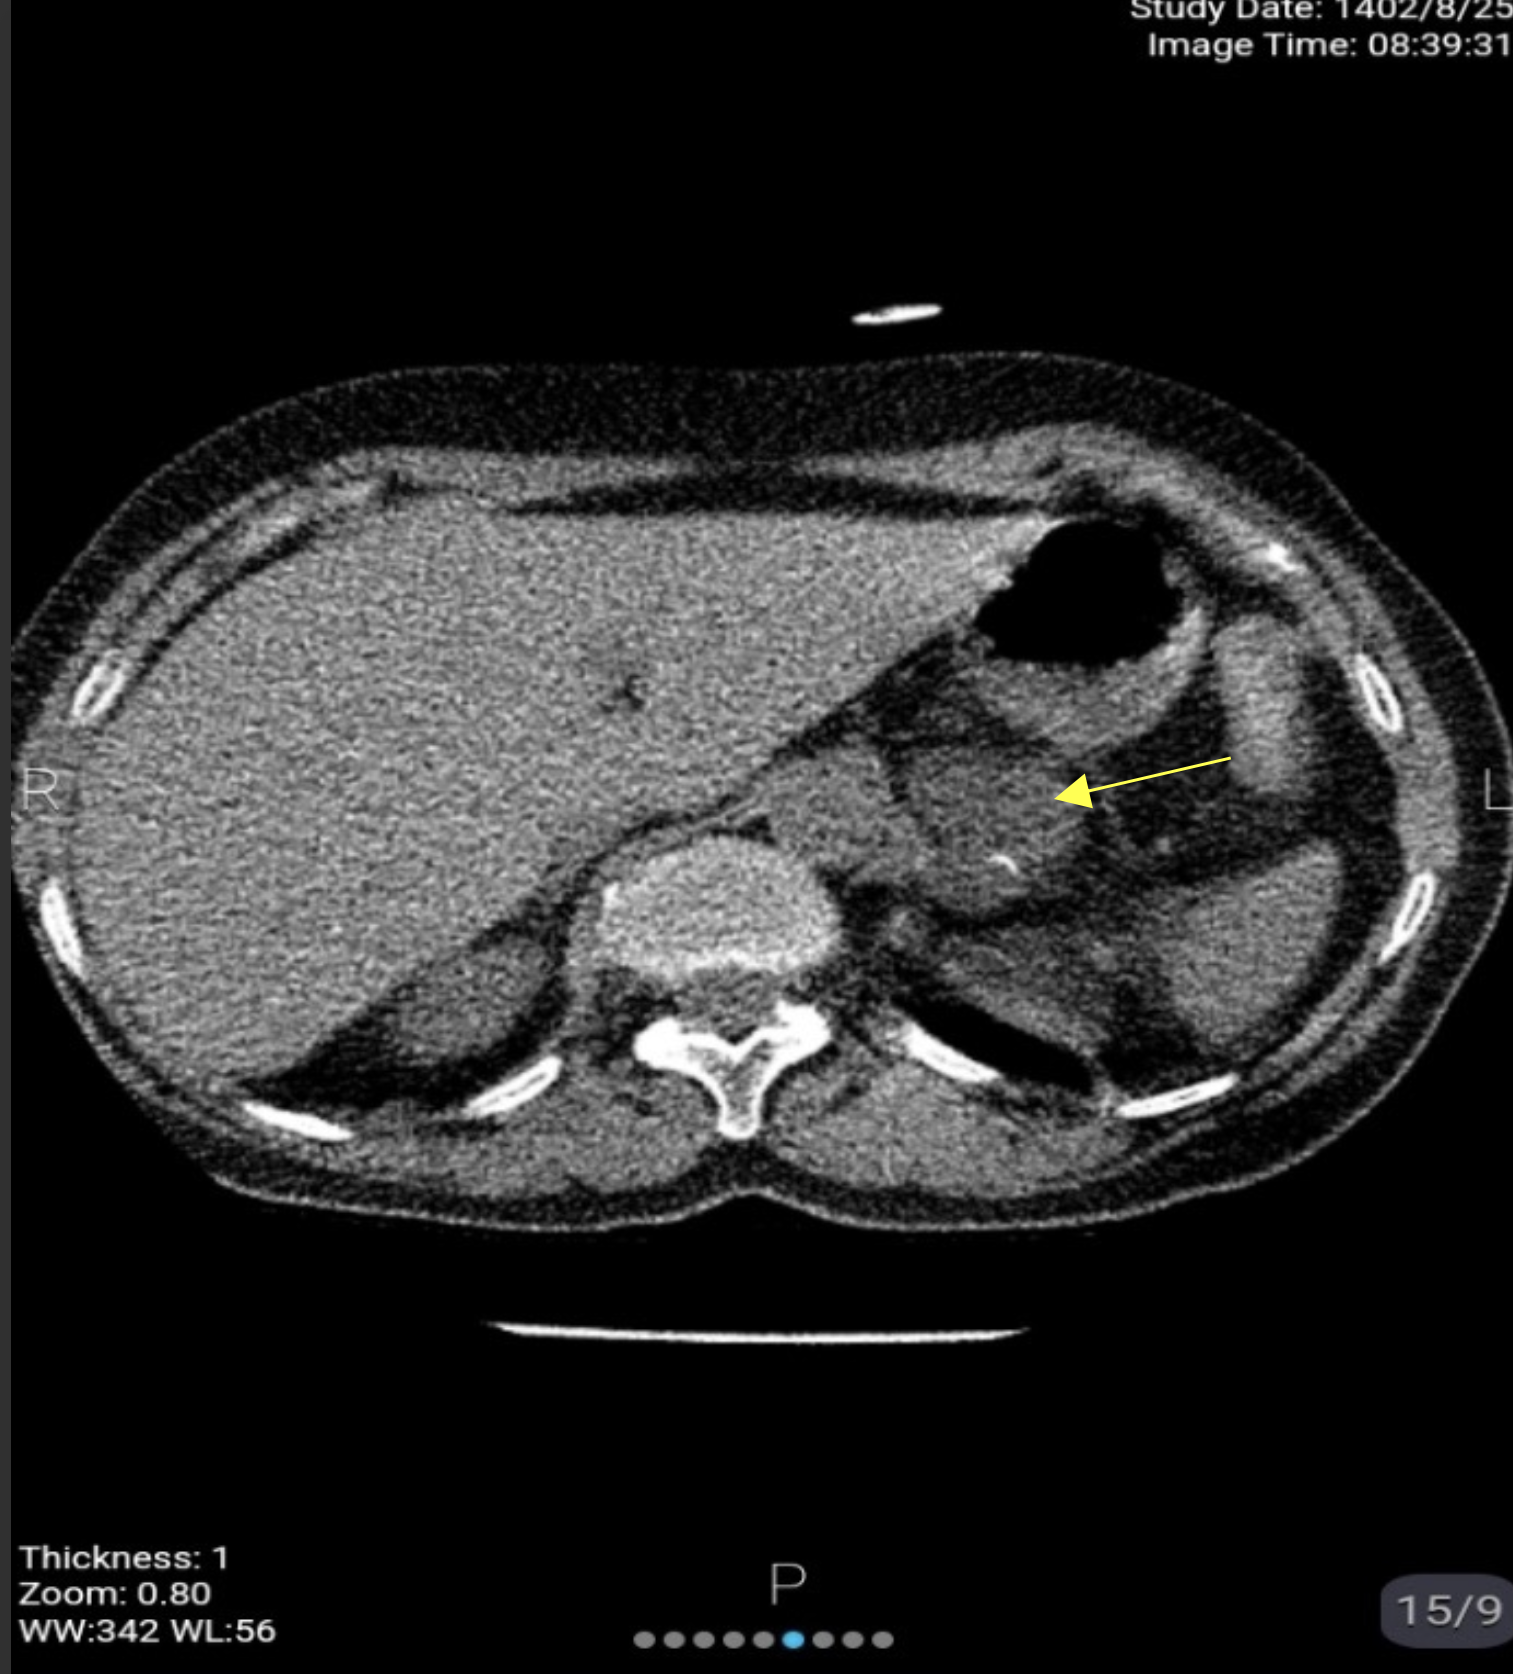

A 60-year-old female patient presented with dyspnea,which was subsequently attributed to bronchiectasis. During a routine lung computed tomography (CT) scan, incidental imaging of the upper abdomen revealed a left adrenal mass measuring 40 mm in diameter with a Hounsfield Unit (HU) value exceeding 10. The patient reported no associated symptoms such as flank pain, hypertension, or headaches.

Further diagnostic imaging was performed, including an adrenal wash out CT protocol. The latter confirmed a well-defined mass originating from the left adrenal gland, measuring 35x40 mm. The lesion exhibited calcified components and heterogeneous enhancement, with a relative washout of <40% and an absolute washout of <60%. These imaging characteristics were inconsistent with a benign adrenal adenoma.

The patient was a 60-year-old woman who underwent lung CT scan due to Dyspnoea which later was found to be due to bronchiectasis. . In limited cuts from the upper part of the abdomen, a 40 mm left adrenal mass with HU>10 was seen in the lung CT scan. The patient did not mention any related complaints such as flank pain, increased blood pressure, headache, etc. The patient underwent further investigation (Figure 1-4).

Fig1. Spiral lung CT Scan Without contrast

Fig2. Spiral abdominopelvic CT Scan without and with intravenous contrast

Fig3. Spiral abdominopelvic CT Scan without contrast

Fig4. Spiral abdominopelvic CT Scan with intravenous contrast